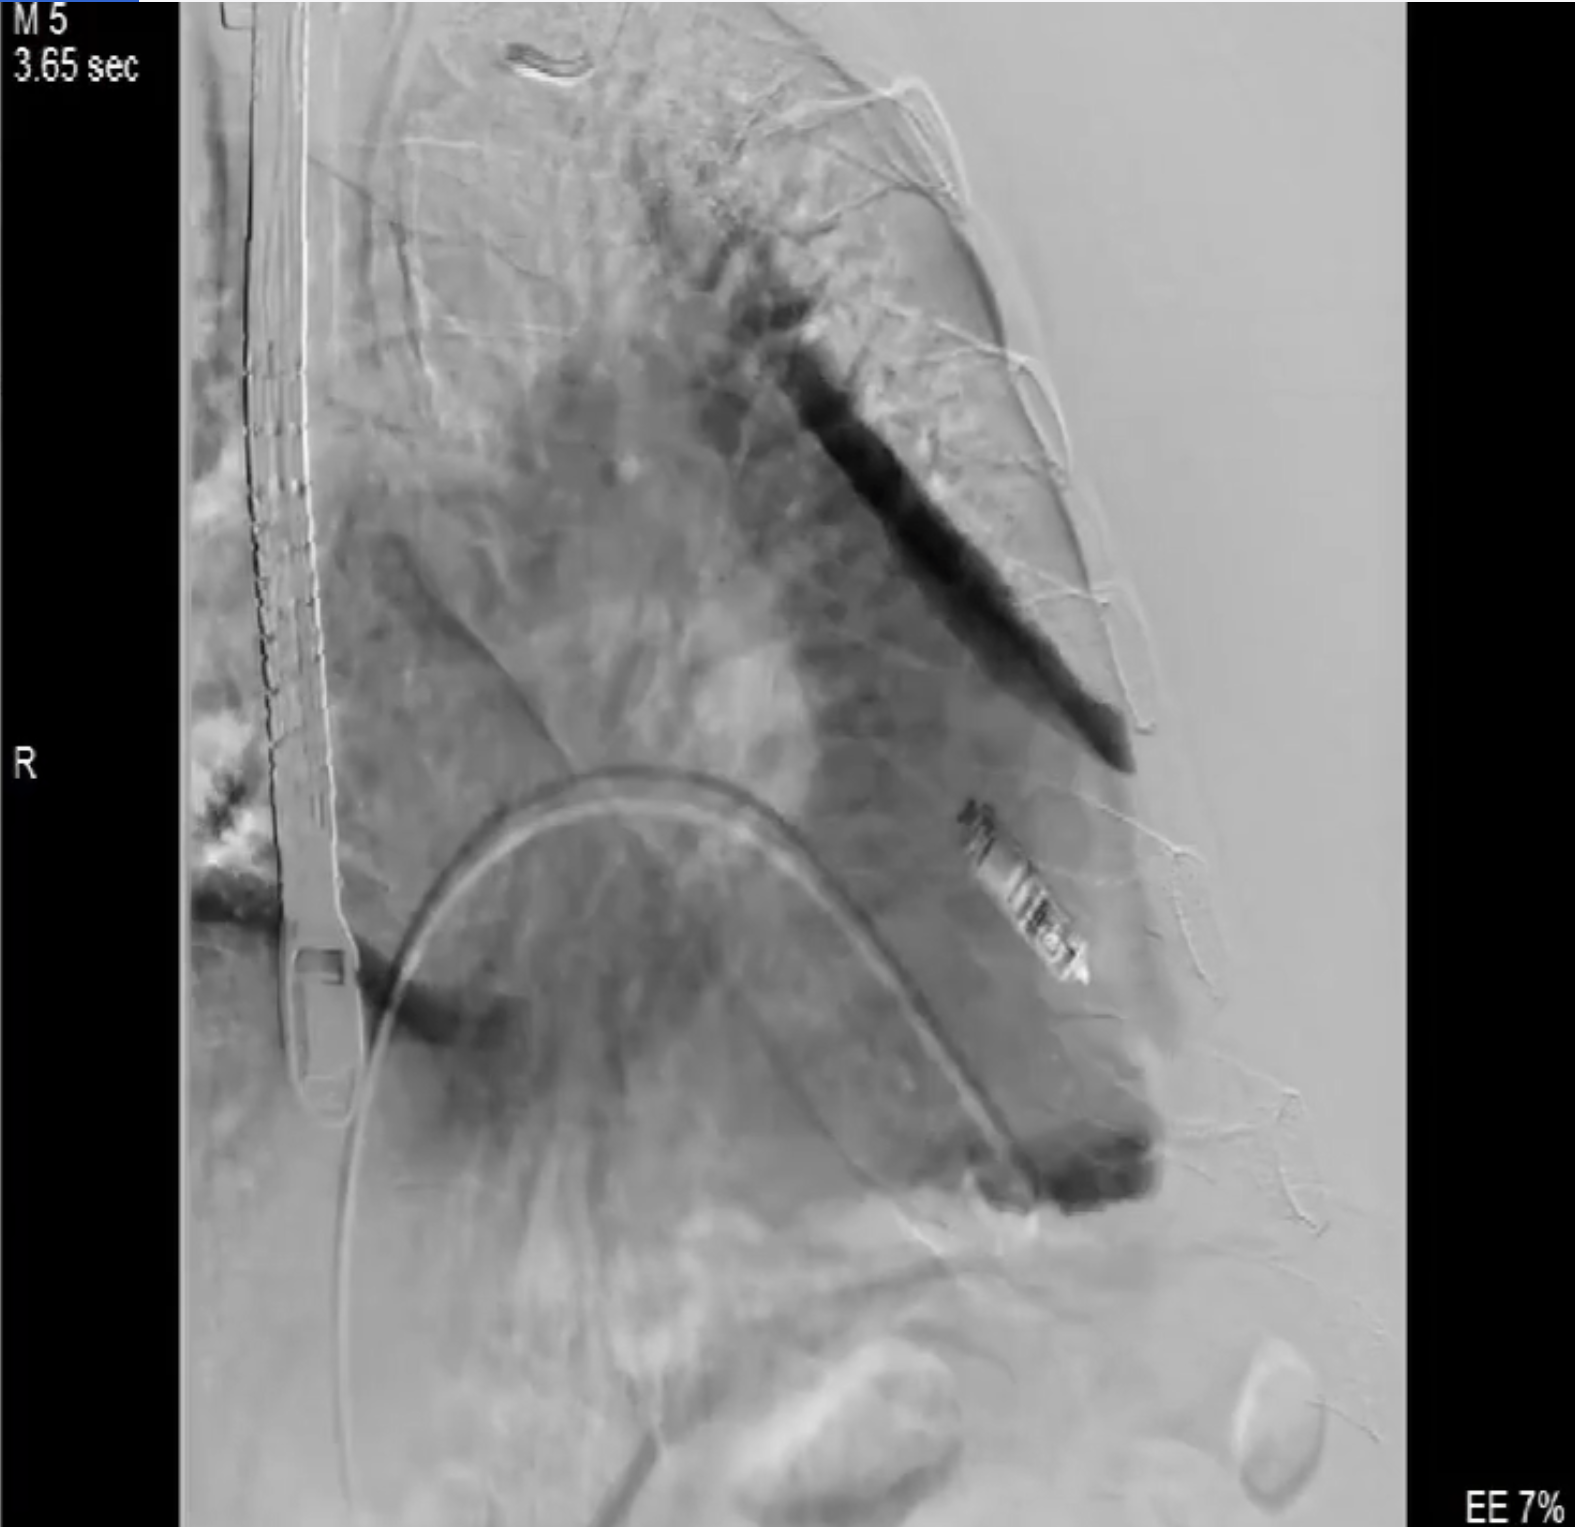

術(shù)中影像

術(shù)前DSA造影可見三尖瓣大量返流呈瀑布樣,右室偏間隔側(cè)可見無導線起搏器一枚。